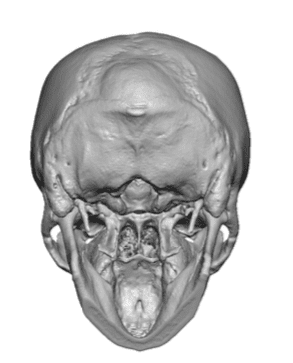

Desire for a higher and more prominent crown of the skull.

Crown of skull augmentation using a custom skull implant.

Desire for a higher and more prominent crown of the skull.

Crown of skull augmentation using a custom skull implant.